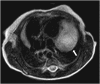

Hamartomas are tumours composed of mesenchymal tissues such as cartilage, fat, connective tissue and smooth muscle and can be found in virtually any organ system. These masses commonly develop sporadically, but are also seen in certain syndromes such as tuberous sclerosis or Carney triad. While their imaging appearance varies depending on the organ they arise from, findings are usually unique and a diagnosis can be confidently made. Radiologists must be aware of the clinical and imaging presentations of these lesions with the particular goal of avoiding unnecessary studies or invasive procedures. Furthermore, knowledge of common syndromic entities is crucial, as the radiologist may be the first to suggest the diagnosis.